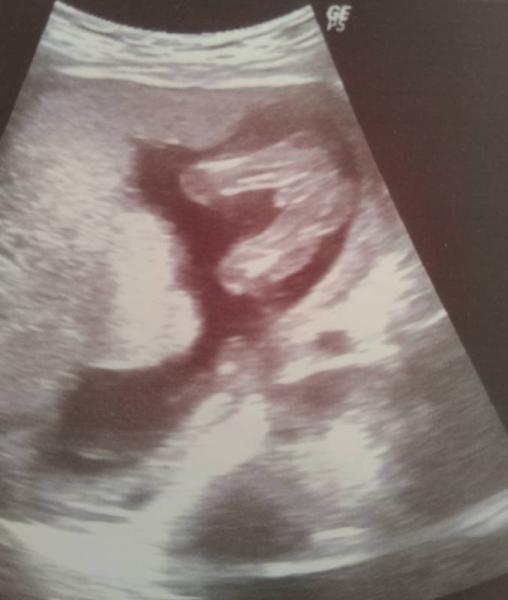

Huhu Also ich esse echt alles von den Gelüsten her müsste man sagen Mädel aber es wird ein Junge das weiß ich seid der 13/14 SSW . Bei meinem großen hab es echt nur Gurken und jetzt bei unseren Hermann gibt es echt alles hauptsächlich Süßigkeiten . Bei meinen Mädels hab ich auch alles gegessen hatte da aber oft Appetit auf fisch . In dieser SS hatte ich auch null Anzeichen.Liebe Grüße Nane29 PS das Bild ist aus Woche 13/14

Bild zu